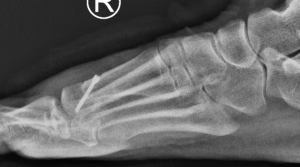

Figure1 and 2: Pre op x-rays showing joint degenerating including joint space narrowing, bone spurs and loose bone fragments.

Figure 2: Post op x rays showing the joint remodelled (spurs removed) and the decompression osteotomy/bone cut allowing for improved joint motion